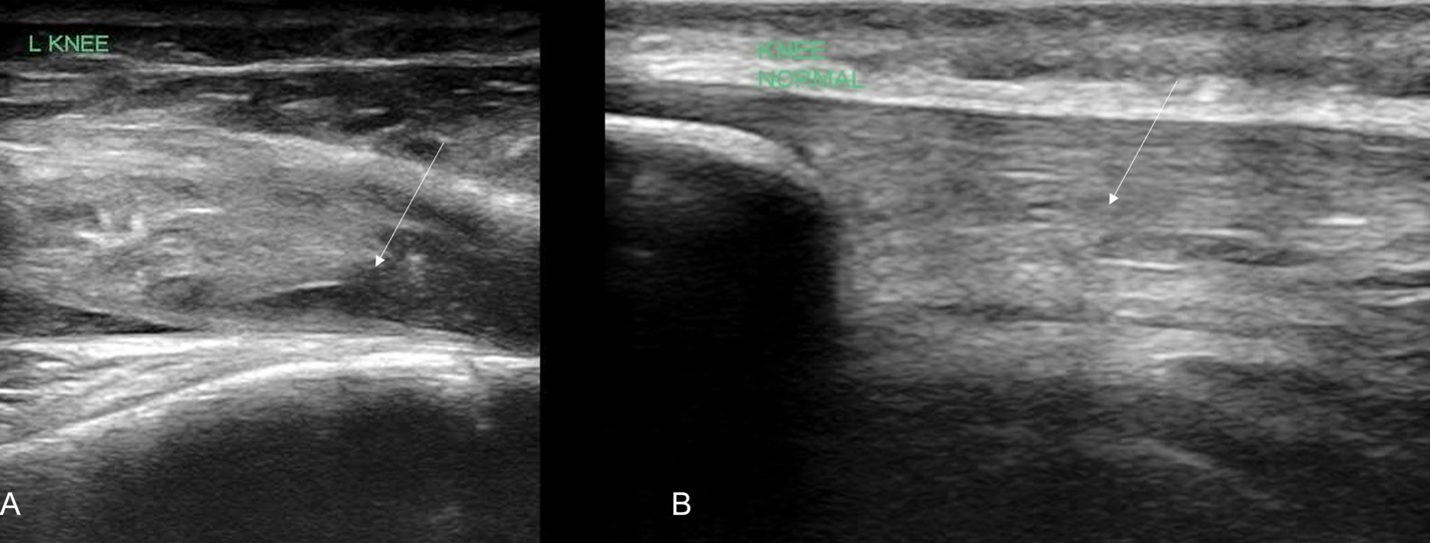

In our case report, we successfully identified key features suggestive of tibial tubercle fractures: disruption of the patellar tendon, posterior acoustic shadowing of a bone fragment, and a large joint effusion. To perform knee ultrasound, the linear probe should be used and placed inferior to the patella in sagittal plane. The patellar tendon should be visualized in two planes, fanning through it completely (Video 1), and compared to the contralateral normal knee. (Figure 4) Abnormal findings suggestive of epiphyseal fractures include disruption of the tendon, an increased hypoechoic space adjacent to or posterior to the tendon (suggestive of either hemarthrosis or a hematoma), or a hypoechoic zone (ie, posterior acoustic shadowing due to an avulsed bony fragment).3,4

Figure 4: A) Ruptured tendon (arrow) in comparison against (B) contralateral knee indicating the normal continuous tendon fibers (arrow)